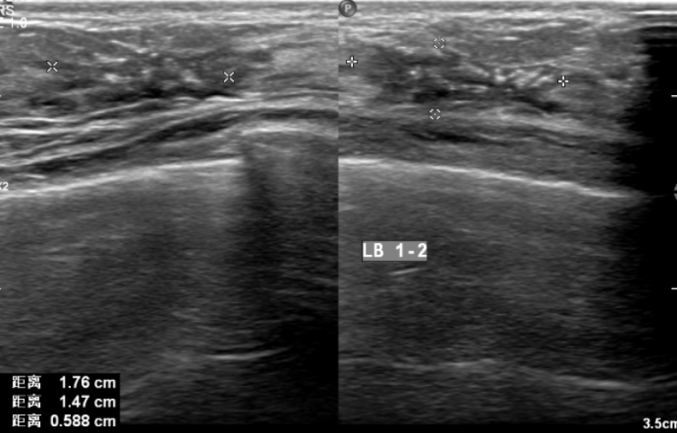

2021-6-9乳腺及腋窝淋巴结超声:左侧乳腺外上象限见大小约45*21mm低回声团块,边界不清,形态不规则,肿块前缘达皮肤层,内回声不均匀,内见多枚杂乱强光点,可见血流信号,测其动脉血流RI0.76。余双侧乳腺腺体形态、结构未见异常。左侧腋窝见多枚低回声结节,边界清,形态饱满,有包膜,内见多发强光点,较大者约13*10mm,内可见血流信号。右侧腋窝未见肿大淋巴结回声。

影像诊断:左侧乳腺低回声团块(BI-RADS:5类,考虑浸润性Ca);左侧腋窝多发异常肿大淋巴结。

图1.乳腺B超(2021-6-9)